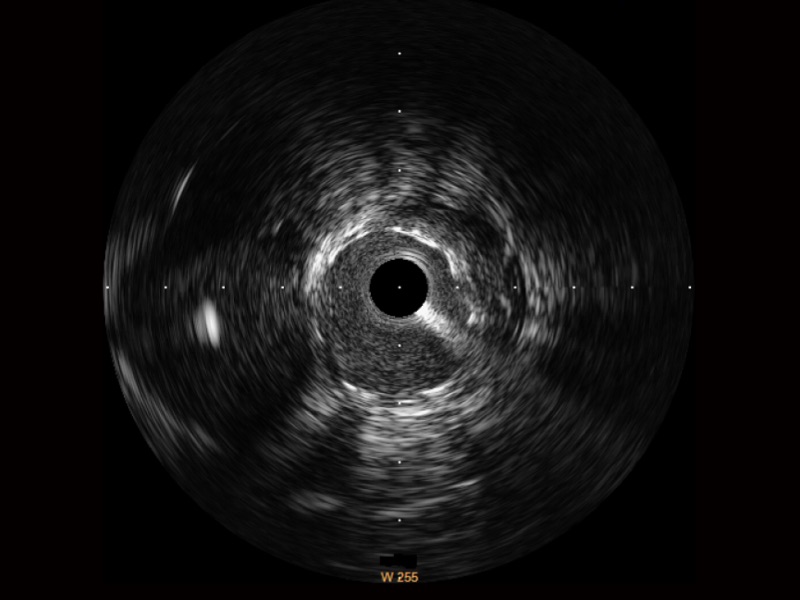

• 16877太阳集团宽频IVUS图像

• 传统IVUS图像

对比传统IVUS导管成像,16877太阳集团宽频IVUS图像的近场支架梁显影更细腻,远场中膜外血管仍清晰可辨,兼顾远中近,兼顾分辨力与穿透深度